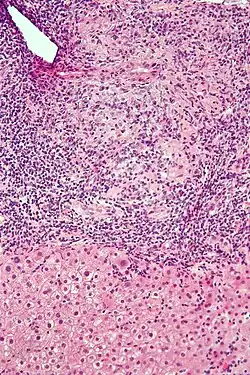

| Micrograph of PBC showing bile duct inflammation and injury, H&E stain | |

Intermediate-magnification micrograph of PBC showing bile duct inflammation and periductal granulomas, liver biopsy, H&E stain -

On microscopic examination of liver biopsy specimens, PBC is characterized by chronic, nonsuppurative inflammation, which surrounds and destroys interlobular and septal bile ducts. These histopathologic findings in primary biliary cholangitis include:[32]

- Inflammation of the bile ducts, characterized by intraepithelial lymphocytes

- Periductal epithelioid granulomas.

- Proliferation of bile ductules

- Fibrosis (scarring)

The Ludwig and Scheuer scoring systems have historically been used to stratify four stages of PBC, with stage 4 indicating the presence of cirrhosis. In the new system of Nakanuma, the stage of disease is based on fibrosis, bile duct loss, and features of cholestasis, i.e. deposition of orcein-positive granules, whereas the grade of necroinflammatory activity is based on cholangitis and interface hepatitis. The accumulation of orcein-positive granules occurs evenly across the PBC liver, which means that staging using the Nakanuma system is more reliable regarding sampling variability.